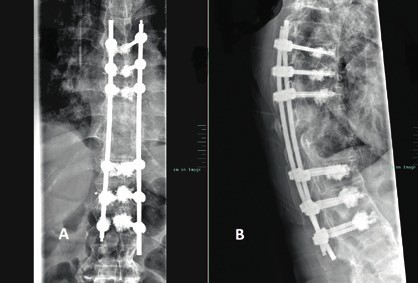

Prinzipiell richtet sich die Entscheidung, welche operative Versorgung durchgeführt wird, nach Ausmaß und Art der Verletzung. Für die Stabilisierung der dorsalen Säule reicht im Falle einer stabilen ventralen Säule die dorsale Instrumentierung aus. Hier gewährleisten dorsale Pedikelschrauben, die mit einem Stab verbunden sind, eine gute Wiederherstellung der Stabilität (Abb. 2). Im Falle einer instabilen ventralen Säule ist hingegen eine Implantation von Wirbelkörperersatz und eine dorsoventrale Segmentversteifung indiziert (Abb. 3). Die entwickelten minimalinvasiven Techniken – zum Beispiel die transkutane Pedikelschraubenimplantation oder der Wirbelkörperersatz durch endoskopische Thorakotomie – haben dazu geführt, dass das Wundgebiet und die operationsbedingte Gewebeschädigung reduziert werden und somit eine Belastungsreduktion für den Körper erzielt wird. Dieser Aspekt ist insbesondere bei älteren Patienten mit multiplen Begleiterkrankungen von Vorteil. Im Falle einer osteoporotischen Wirbelsäule werden die implantierten Pedikelschrauben zementiert (Abb. 4). Auch hier erlaubt die Entwicklung fenestrierter Schrauben eine optimale Möglichkeit der Zementapplikation.